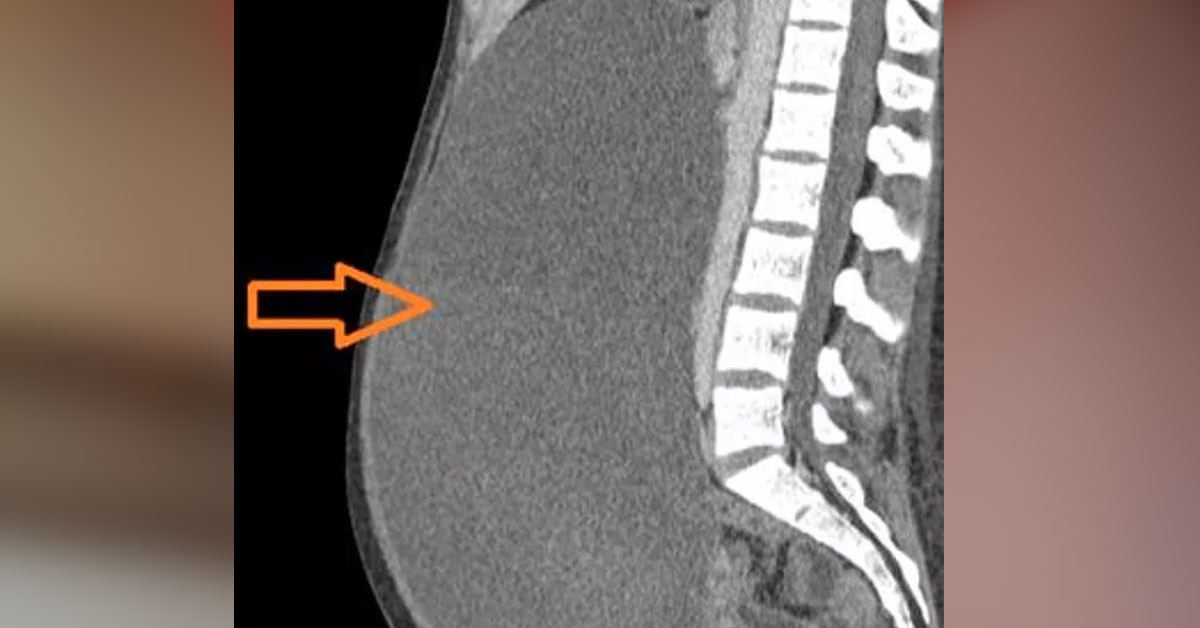

Sarah’ın yaşadığı bu durum tıpla ‘endometriozis’ yani çikolata kisti olarak geçiyor.

“Doktor bana 25 yılllık meslek hayatında daha önce hiç bu kadar kötü bir çikolata kisti görmediğini söyledi.” dedi.